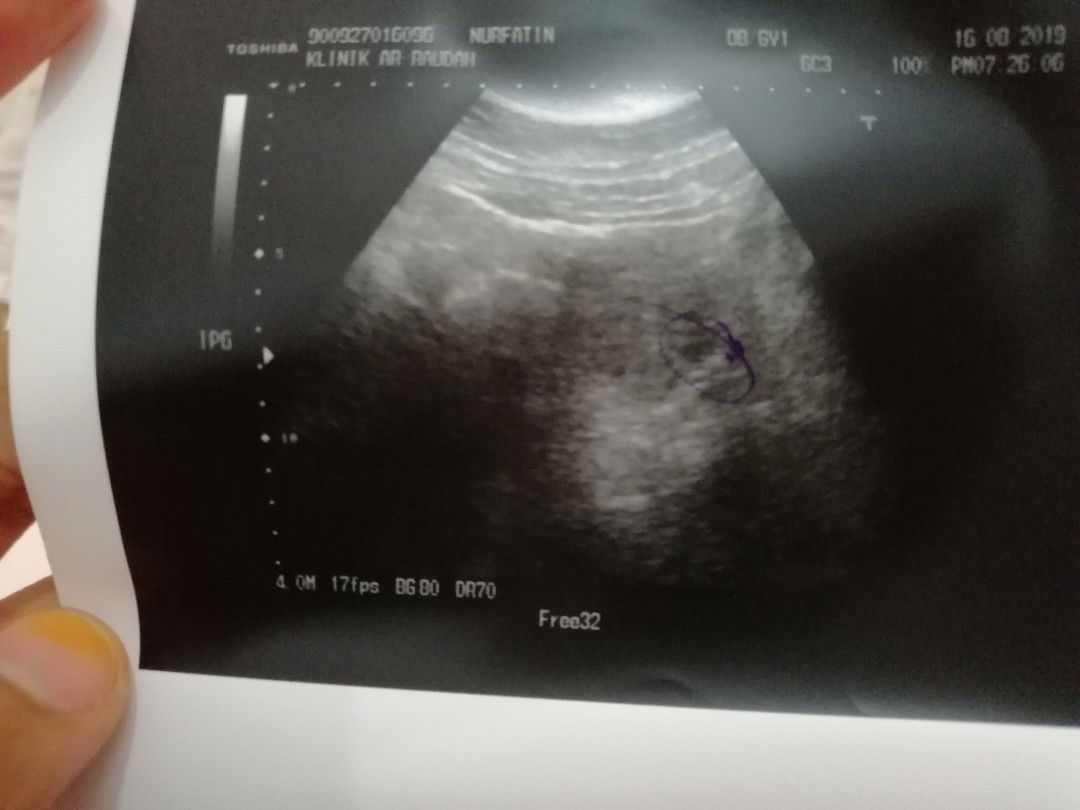

Td saya cek klinik sbb ada pendarahan dari coklat cair ke warna merah. Doc kata 50-50. Sbb kalau tgk dari lewat dtg period, kandungan saya dah masuk 6w6d tapi bila scan kecik sgt then tak nampak sgt. Macam usia baru 3w 4w. Doc kata myb kitaran haid saya xbetul jd kiraan usia kandungan jadi salah atau bby saya mmg xnak membesar. Setakat itu sj. Doc ada kasi ubat kuatkan rahim. Doakan kandungan saya supaya dpt membesar dgn sihat. Ni 1st baby. Nampak mcm tak sedih tapi dalam hati Allah saja yg tahu ?